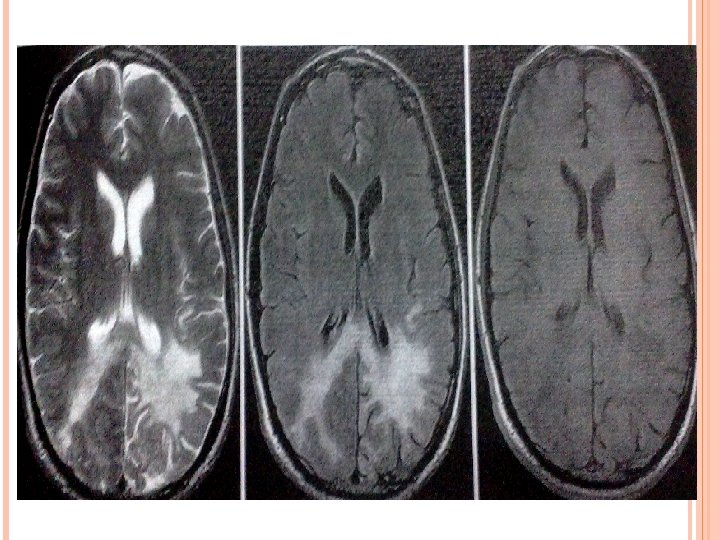

CASEATING WITH LIQUID CENTRE: When the solid centre liquefies it appears hyperintense on T 2 W images with surrounding hypointensity. On post contrast images show rim enhancement.

TUBERCULAR ABCESS Large multiloculated ring enhancing lesions with surrounding edema and mass effect on MRI. DWI shows restricted diffusion with low apparent diffusion coefficient (ADC).